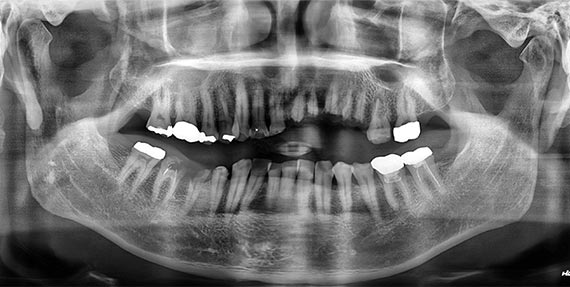

시술 전후 비교

BEFORE

AFTER